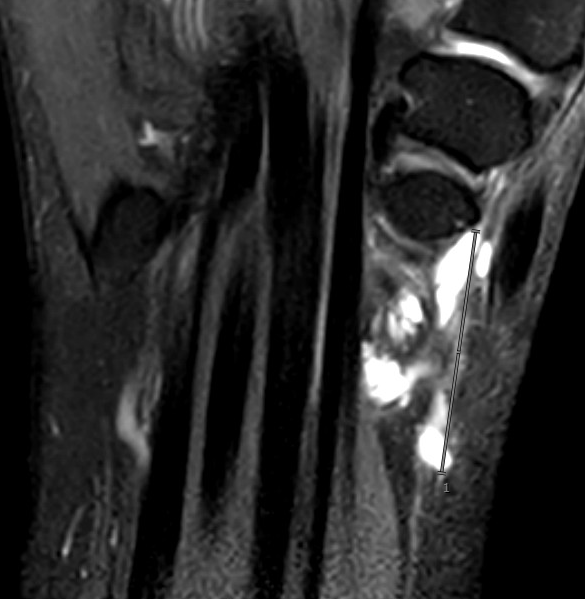

Dorsal ganglion arising from scapholunate joint

Dorsal ganglion arising from scapho-lunate joint